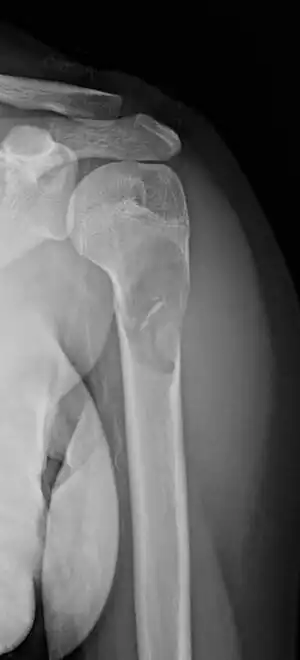

X-ray: Simple bone cyst in left upper arm of 13 year old | |

- Unprovoked break in the long bone of the upper arm,, with "fallen leaf" sign.